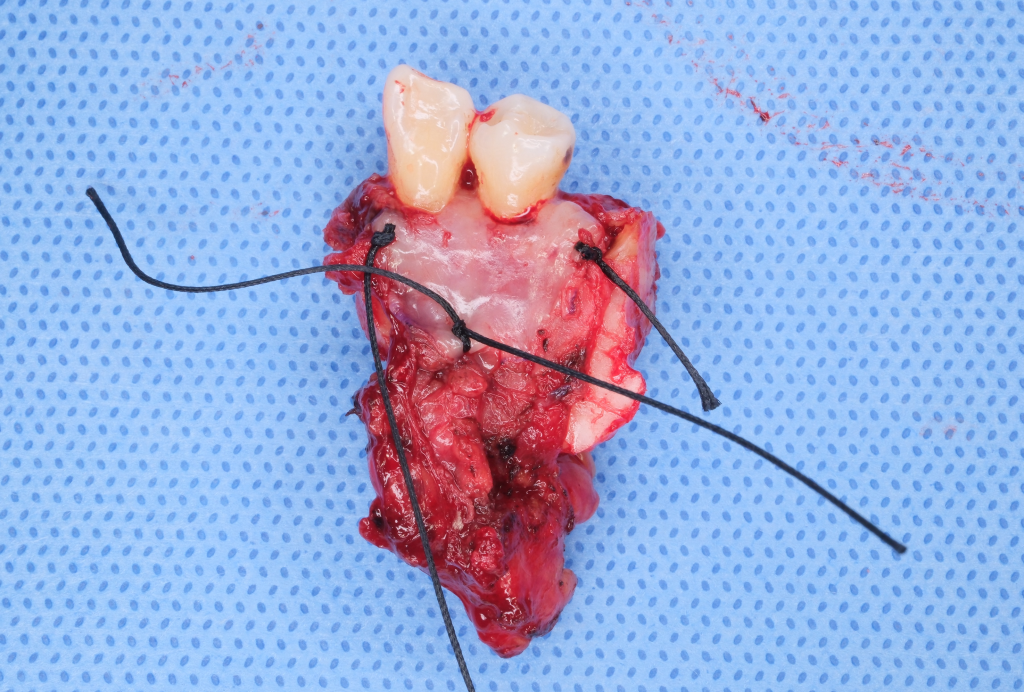

검체는 잘 확보하였으며, 치은에 붙어있던 연부조직과 일괄절제하였습니다. 안전역 확인을 위한 동결절편검사 후라 점막이 일부 적어보이나, 실제로는 2~3mm 더 여유있게 제거하였습니다.

수술 결과 고분화도의 편평세포암종으로, 6mm x 3mm 의 크기이며, 이형성(dysplasia)는 암종 부위를 포함하여 1.6 x 0.8x 0.4cm 의 크기로 분포하였습니다. 침윤은 2.7mm, 안전역은 전 방향에서 5mm이상을 얻어 추가 치료 필요없는 pT1의 병기를 얻었습니다. 함께 제거한 하악골에서도 종양의 침윤은 없어, 좋은 결과를 확인할 수 있었습니다.